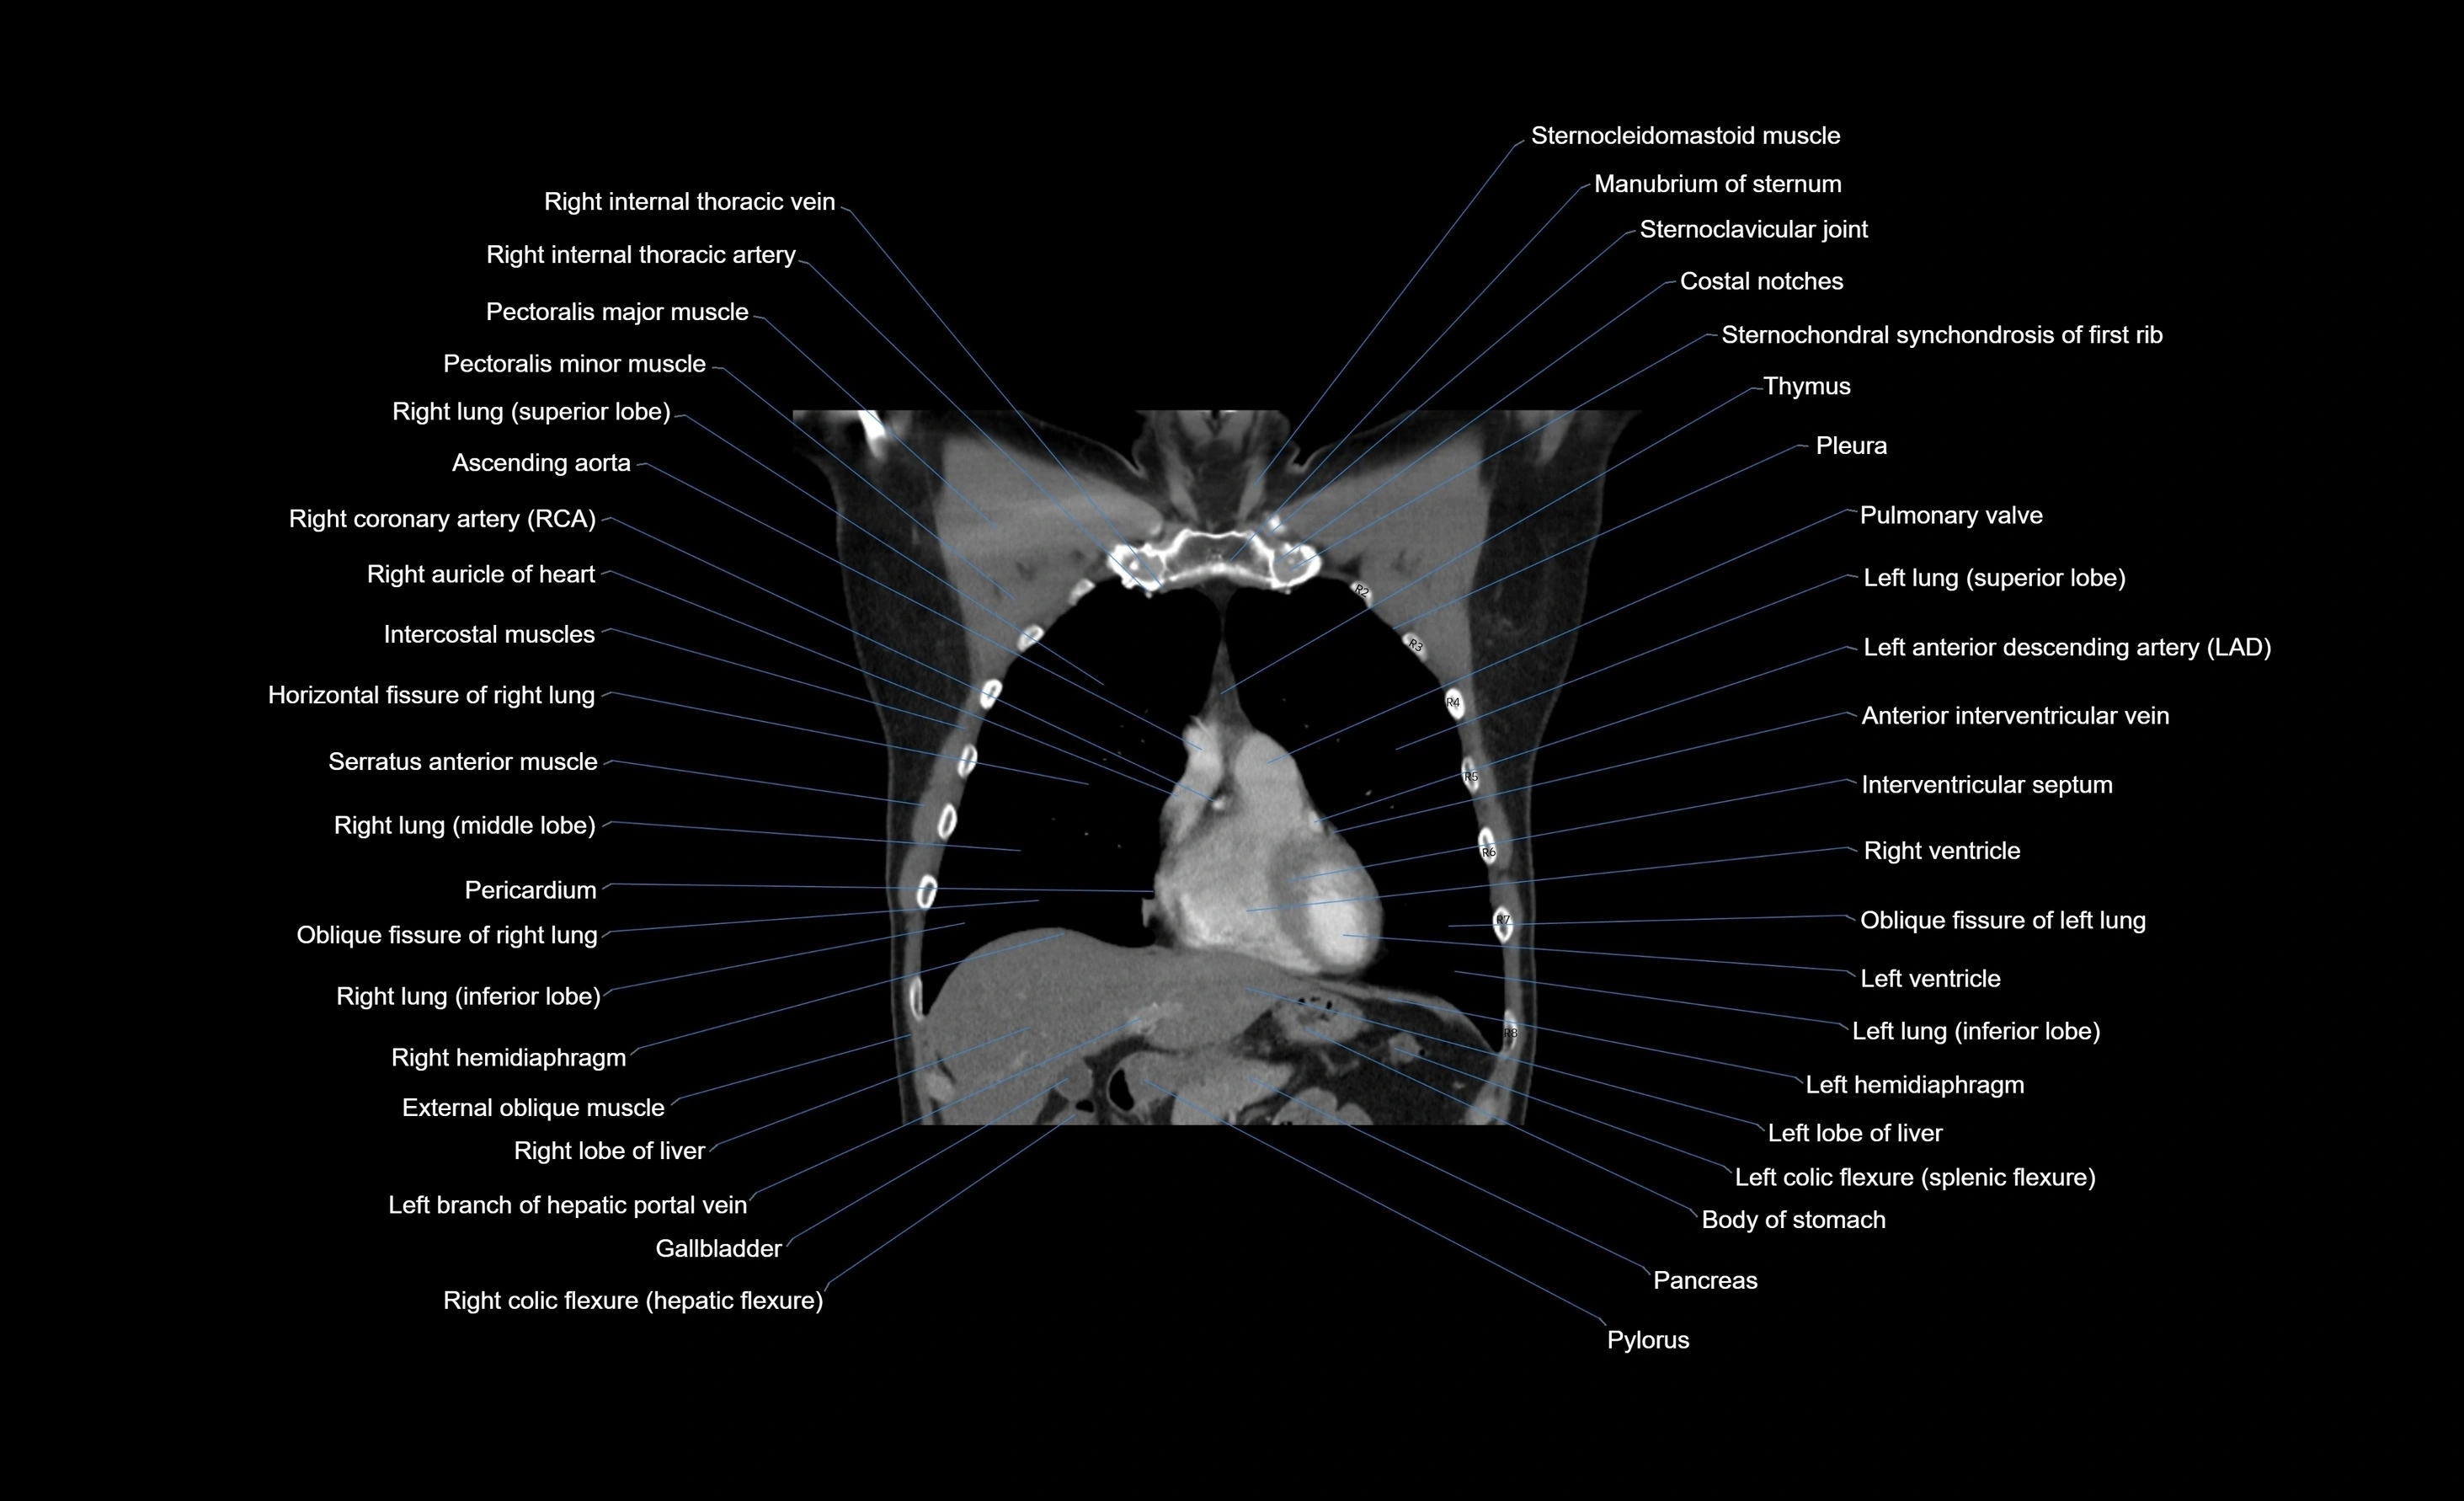

CT images